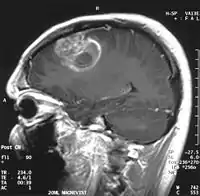

En las imágenes de TC y RM se muestra como una lesión heterogénea, de contorno irregular, que capta contraste en anillo y con un área central necrótica.

Diagnóstico por imagen y glioblastoma

La TC muestra una lesión de morfología irregular, predominantemente hipodensa y fuertemente dishomogénea, debido a la presencia de grandes áreas necróticas de más clara hipodensidad y de áreas sólidas hiperdensas. Estas últimas son la expresión de un rápido crecimiento y por lo tanto de una elevada malignidad. Son frecuentes las zonas hemorrágicas, que van desde pequeños focos a grandes áreas hemáticas que pueden cubrir toda la lesión. Es característica la morfología en "mariposa" si el tumor se asienta en ambos hemisferios a través del cuerpo calloso.

Tras la aplicación de contraste aparecen gruesos anillos alrededor de las áreas necróticas. En la RM, la parte sólida aparece hipointensa en T1 e hiperintensa en T2 con zonas de señal más elevada en las partes de mayor celularidad. Las áreas necróticas, hiperintensas en T2, pueden presentarse hipo-, iso- o hiperintensas en T1 en función del contenido proteico o de productos de la degradación de la hemoglobina. El realce tras el contraste suele ser intenso e irregular en la periferia del tumor e identifica sobre todo la componente celular "proliferativa" de la neoplasia. Son comunes las áreas puntiformes y serpiginosas de ausencia de señal de flujo, asociadas a la presencia de una neovascularización rica. Estos vasos de neoformación patológica carecen de barrera hematoencefálica, lo que explica tanto la abundante impregnación como el edema vasogénico perilesional (véase la sección anterior), debido al paso de líquido al medio extracelular.[71][72]